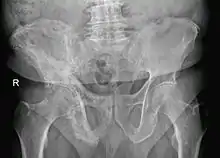

Los hallazgos radiológicos se centran sobre todo en el fémur, cráneo, tibia, espina lumbosacra, clavículas y costillas. Los huesos pequeños no son, por el general afectados. Los más característicos se encuentran en el raquis y el cráneo: en el raquis se puede observar una trabeculación basta vertical o áreas de esclerosis en banda en las plataformas. En el cráneo se observan zonas radiolucentes en los huesos frontales, parietales y occipitales. En la fase avanzada hay un ensanchamiento y engrosamiento de todo el cráneo con zonas con manchas de mayor densidad. En los huesos largos, se observan frecuentemente zonas perpendiculares radiolucentes sobre todo en la parte convexa de la tibia y el fémur, que representan zonas líticas. Los cambios en la pelvis reflejan la variación de la resorción ósea y formación de hueso nuevo y a menudo va acompañada de un engrosamiento en las alas de la misma.